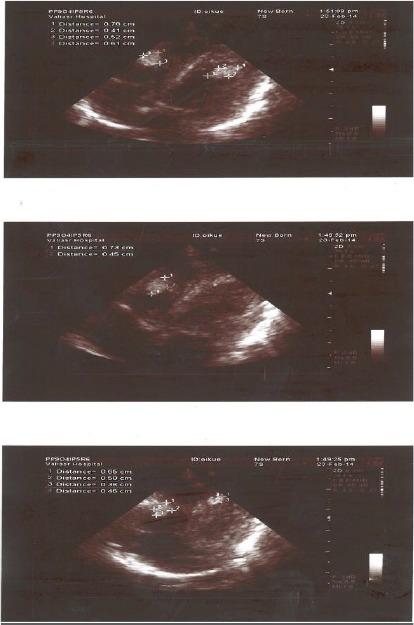

Tuberous Sclerosis Complex (TSC) is an autosomal-dominant hereditary disorder. This syndrome is characterized by tumor-like malformations in several organs, as well as the heart. This report summarizes a case of TSC in a premature infant, born at 34 weeks' gestation with ascites. After birth, multiple cardiac mass, subependymal cysts and hypopigmented macules were detected. To our knowledge, this is the first case report of early onset of TSC with chylous ascites in Iran.

结节性硬化症(TSC)是一种常染色体显性遗传性疾病。该综合征的特征是多个器官以及心脏出现肿瘤样畸形。本报告总结了一例早产34周并伴有腹水的结节性硬化症患儿病例。出生后,检测到多处心脏肿块、室管膜下囊肿和色素减退斑。据我们所知,这是伊朗首例伴有乳糜性腹水的早发性结节性硬化症病例报告。